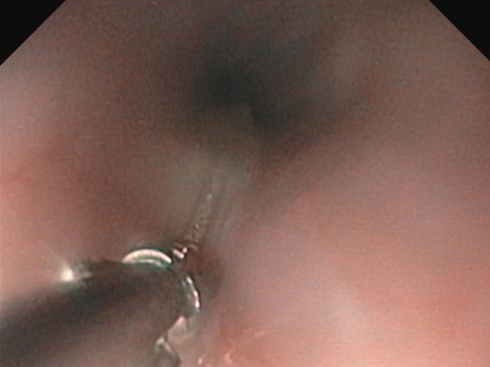

鼻腔内視鏡の様子:Jターン

鼻腔内視鏡の様子:内視鏡での狭窄部位